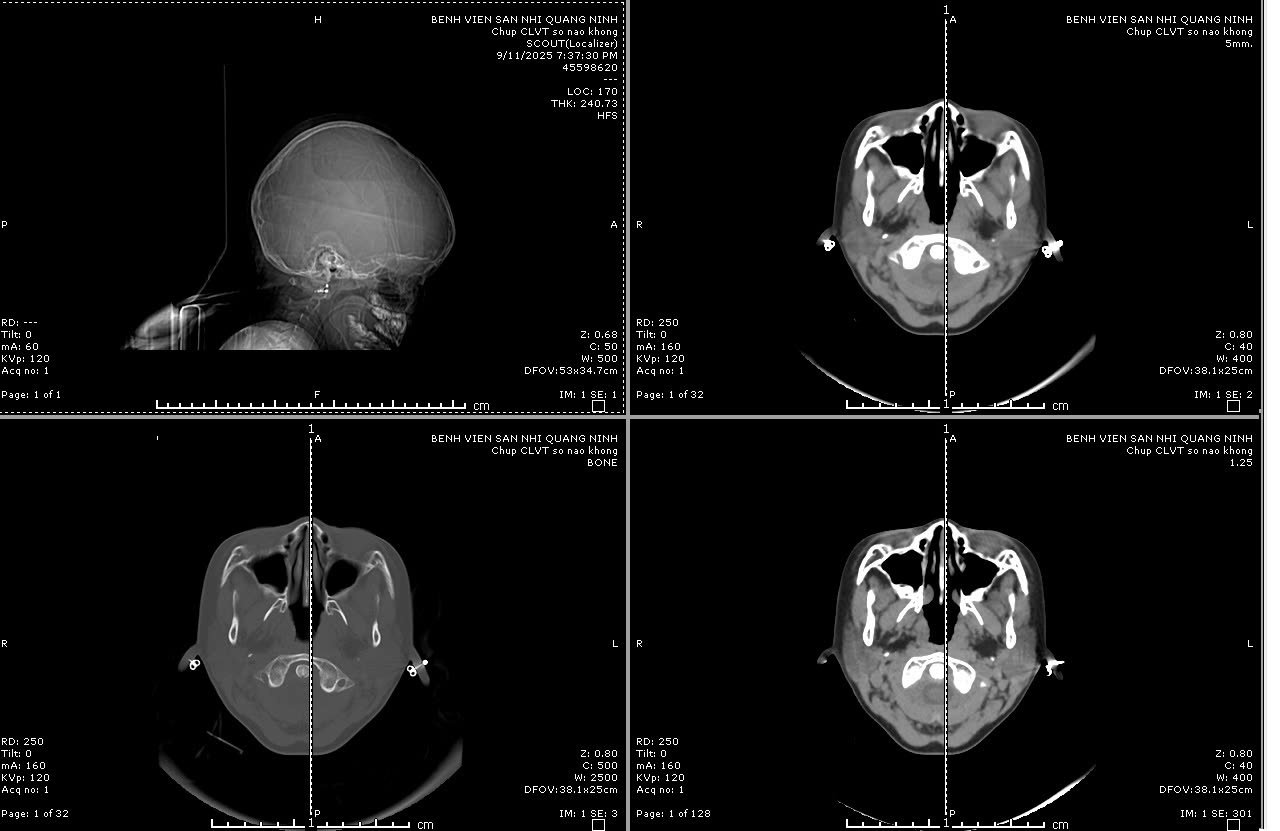

Sau khi tiếp nhận, Bệnh viện đã kích hoạt quy trình báo động đỏ toàn viện: trẻ được các bác sĩ đã nhanh chóng xử trí hồi sức, cấp cứu suy hô hấp, cấp cứu ngừng tim, ngừng tuần hoàn, chăm sóc tích cực và thực hiện các cận lâm sàng. Kết quả cho thấy trẻ bị vỡ xương sọ phức tạp kèm theo chảy máu và dập não phức tạp

Các bác sĩ chuyên ngành ngoại thần kinh nhi của Bệnh viện Sản Nhi đã tiến hành phối hợp hội chẩn liên viện với chuyên gia ngoại thần kinh của Bệnh viện Đa khoa tỉnh; Trẻ được chẩn đoán trẻ bị xuất huyết nội sọ do chấn thương sọ não, tăng áp lực nội sọ, suy hô hấp và nhanh chóng được chuyển phòng mổ chỉ định mổ cấp cứu chấn thương sọ não cho trẻ.